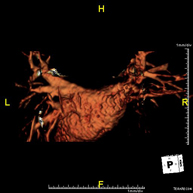

Prueba diagnóstica no invasiva que consiste en el estudio de la arteria aorta abdominal, obteniendo imágenes de alta definición anatómica mediante el empleo de un campo electromagnético y ondas de radio (con un emisor y un receptor). Es indispensable el uso de contraste paramagnético (Gadolinio). Sin embargo, no utiliza radiación ionizante. La calidad de las imágenes permite realizar reconstrucciones en 2D y 3D. Está indicado en aquellos pacientes con enfermedad vascular (aterosclerosis), estudio de aneurismas, en estudios pre-quirúrgicos de lesiones adyacentes a la aorta abdominal como "mapa" vascular, etc. - Angio RM Aorta-ilíaca

Prueba diagnóstica no invasiva que consiste en el estudio de la arteria aorta abdominal de las arterias ilíacas, obteniendo imágenes de alta definición anatómica mediante el empleo de un campo electromagnético y ondas de radio (con un emisor y un receptor). Es indispensable el uso de contraste paramagnético (Gadolinio). Sin embargo, no utiliza radiación ionizante. La calidad de las imágenes permite realizar reconstrucciones en 2D y 3D. Esta prueba está especialmente indicada como estudio pre-quirúrgico (mapa vascular) antes de intervenciones percutáneas o quirúrgicas de aorta abdominal y arterias ilíacas, estudio complementario en pacientes con isquemia de miembros inferiores, etc. - Angio RM Arterial extremidades inferiores

Prueba diagnóstica no invasiva que consiste en el estudio de la arteria aorta abdominal, obteniendo imágenes de alta definición anatómica mediante el empleo de un campo electromagnético y ondas de radio (con un emisor y un receptor). Es indispensable el uso de contraste intravenoso paramagnético (gadolinio). Sin embargo, no utiliza radiación ionizante. La calidad de las imágenes permite realizar reconstrucciones en 2D y 3D. Está indicado en aquellos pacientes con enfermedad vascular (aterosclerosis), estudio de aneurismas, en estudios pre-quirúrgicos de lesiones adyacentes a la aorta abdominal como "mapa" vascular… - Angio-RM Aorta iliaca

Prueba diagnóstica no invasiva que consiste en el estudio de la arteria aorta abdominal, obteniendo imágenes de alta definición anatómica mediante el empleo de un campo electromagnético y ondas de radio (con un emisor y un receptor). Es indispensable el uso de contraste intravenoso paramagnético (gadolinio). Sin embargo, no utiliza radiación ionizante. La calidad de las imágenes permite realizar reconstrucciones en 2D y 3D. Esta prueba está especialmente indicada como estudio pre-quirúrgico (mapa vascular) antes de intervenciones percutáneas o quirúrgicas de aorta abdominal, estudio complementario en pacientes con isquemia de miembros inferiores… - Angio-RM Arterias renales